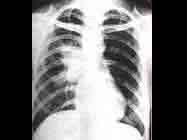

问题 1岁患儿,已患肺炎1周。昨日午后全身中毒症状加重,高热持续不退,呼吸困难加重,频繁咳嗽,面色发绀。血压10.6/8.0kPa(80/60mmHg),胸片见图。考虑此患儿可能是 ( )

选项 A、肺脓肿 B、DIC C、中毒性脑病 D、休克 E、心力衰竭

答案 A